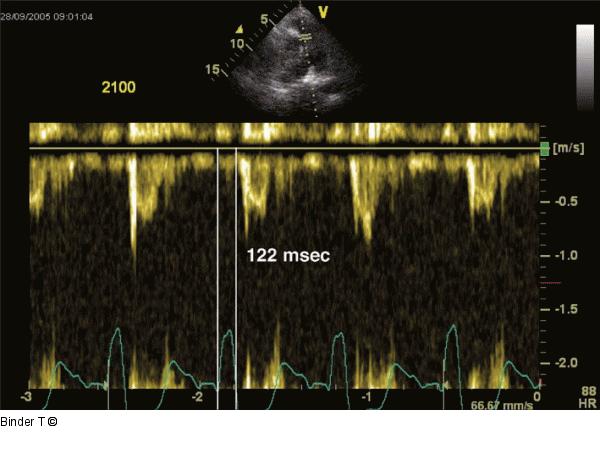

Abbildung 11: Pulmonales elektromechanischer Delay (P-EMD) PW-Dopplersignal des Pulmonalarterienflusses: Bestimmung des pulmonalen elektromechanischen "Delays" (Beginn des QRS-Komplexes bis zum Beginn des Pulmonalflusses). Diese Messung ist erforderlich, um das Interventrikuläre Mechanische Delay IVMD zu bestimmen. Die P-EMD beträgt 122 msec. Beachte: sehr kurze Akzelerationszeit des Pulmonalarterienflusses (70 msec). Dies spricht für eine pulmonale Hypertension. |

Abbildung 11: Pulmonales elektromechanischer Delay (P-EMD)

PW-Dopplersignal des Pulmonalarterienflusses: Bestimmung des pulmonalen elektromechanischen "Delays" (Beginn des QRS-Komplexes bis zum Beginn des Pulmonalflusses). Diese Messung ist erforderlich, um das Interventrikuläre Mechanische Delay IVMD zu bestimmen. Die P-EMD beträgt 122 msec. Beachte: sehr kurze Akzelerationszeit des Pulmonalarterienflusses (70 msec). Dies spricht für eine pulmonale Hypertension. |